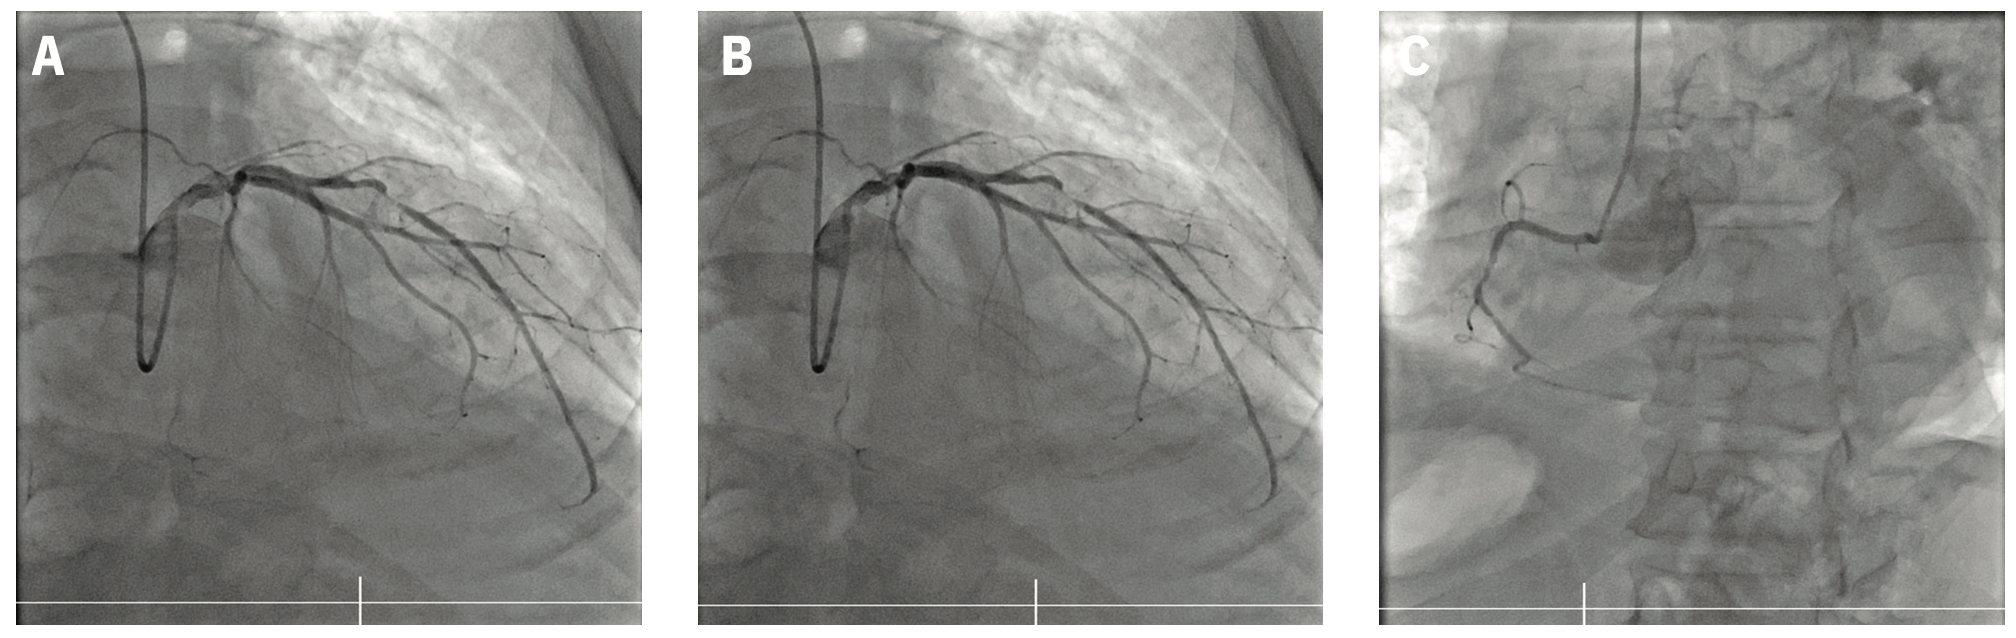

After connecting the guide catheter to the arm of the vascular robotic system (CorPath GRX from Siemens Healthineers), the targeted lesion was crossed by rotating the guidewire automatically upon retraction of the joystick. Intravascular ultrasound-guided PCI was performed to the LAD and LCx at the stent overlap (Figure 1D) using real-time stent positioning verification software (ClearStent Live from Siemens Healthineers). Staged PCI to the totally occluded RCA was performed robotically by again using built-in software automation to rotate the guidewire following joystick retraction to redirect the guidewire tip (Figure 1E), as well as to oscillate the guidewire as it advanced through the vessel (Figure 1F). During the entire case, the primary operator of the vascular robotic system remained in the control room while the secondary operator remained at the patient’s bedside.